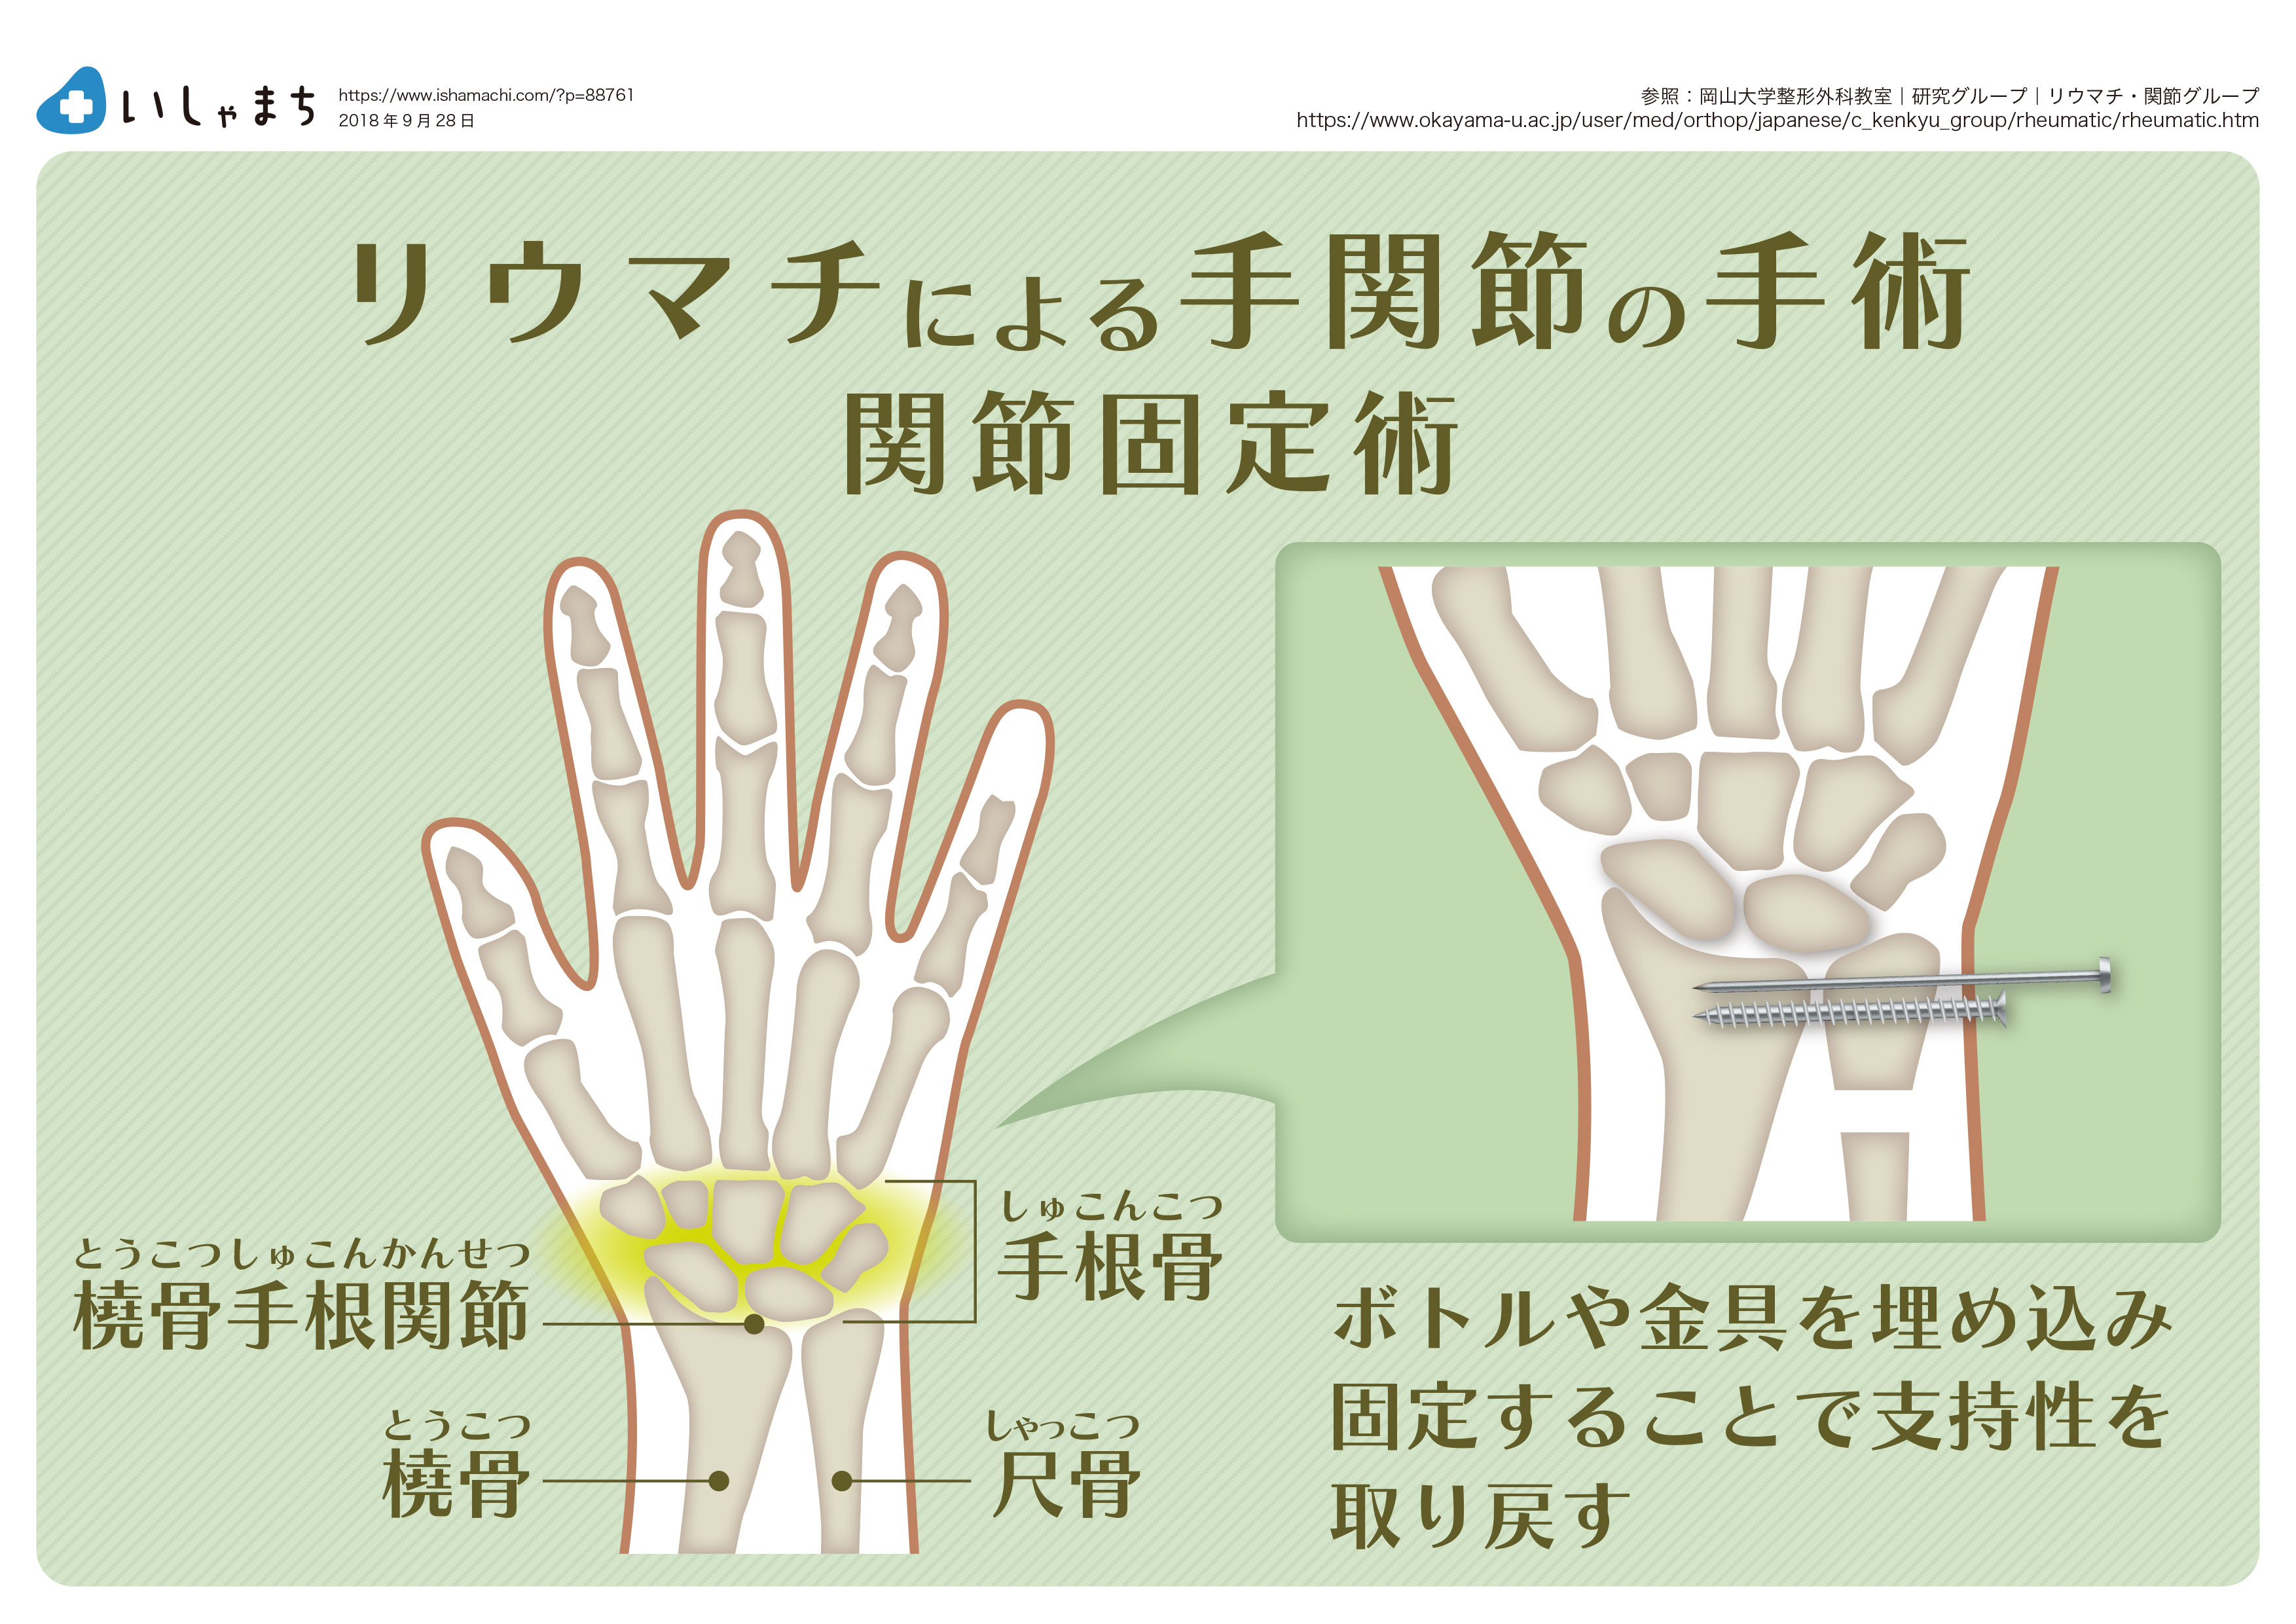

- 癒合(関節固定術):プレートまたはネジを使用して、僧形骨を親指の付け根の長く細い骨に癒合します。